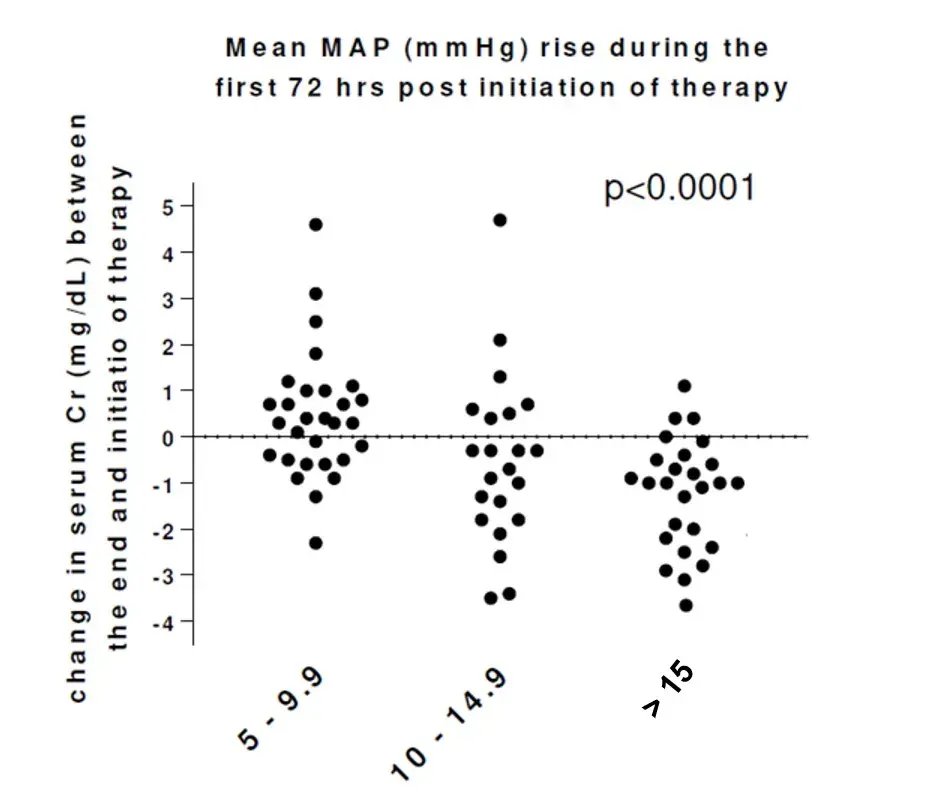

Resistência a diuréticos na insuficiência cardíaca: aumentar o diurético de alça ou associar tiazídico?

Resistência a diuréticos na insuficiência cardíaca: aumentar o diurético de alça ou associar tiazídico?